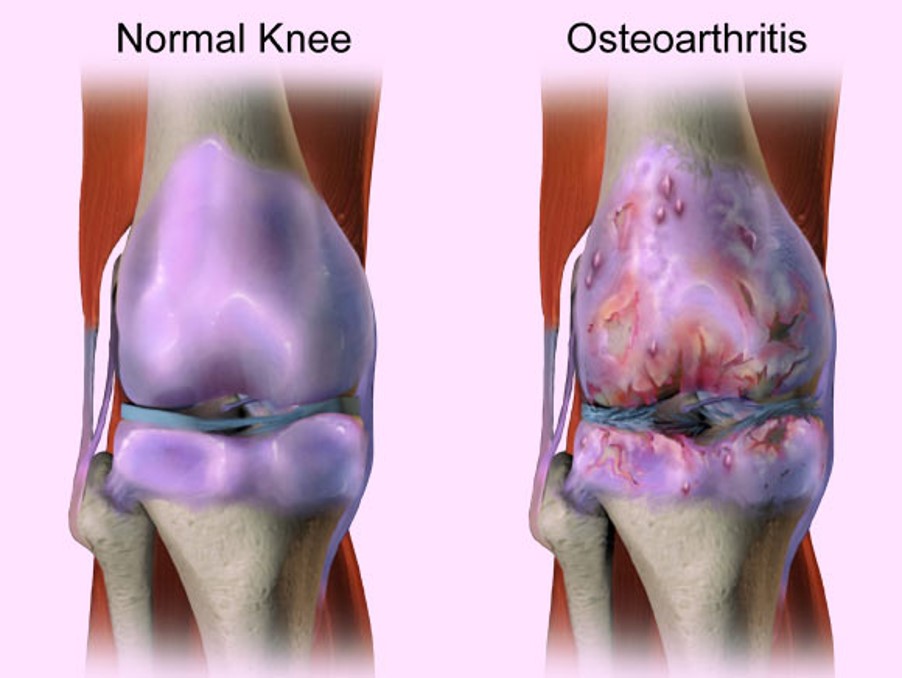

什麼是退化性關節炎?

骨關節炎是最常見的關節炎,全球有數百萬的人們患有此病。隨著時間推移,骨骼末端起緩衝作用的保護性軟骨不斷磨損,就會發生該疾病。

雖然骨關節炎可能損害任何關節,但疾病最常影響膝蓋、髖關節和脊柱中的關節。